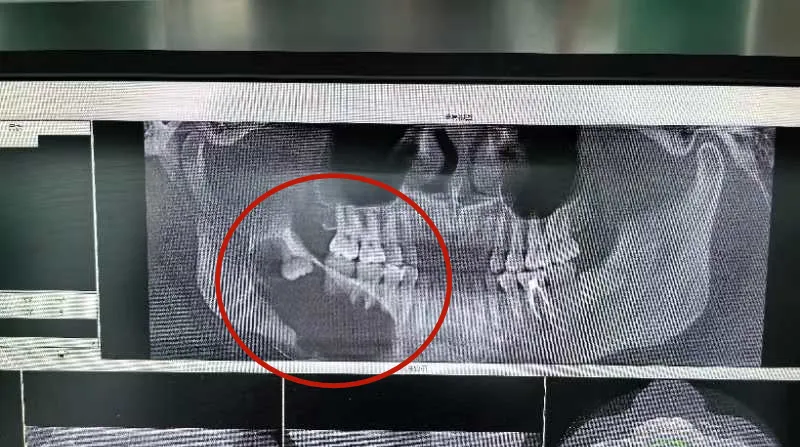

昆山市一医院口腔科立即安排

口腔颌面锥形束CT

结果提示

右下颌第一前磨牙远中至右侧下颌骨升支

见一大小约6.5cm*4.0cm 的椭圆形低密度影

囊腔压迫下牙槽神经管